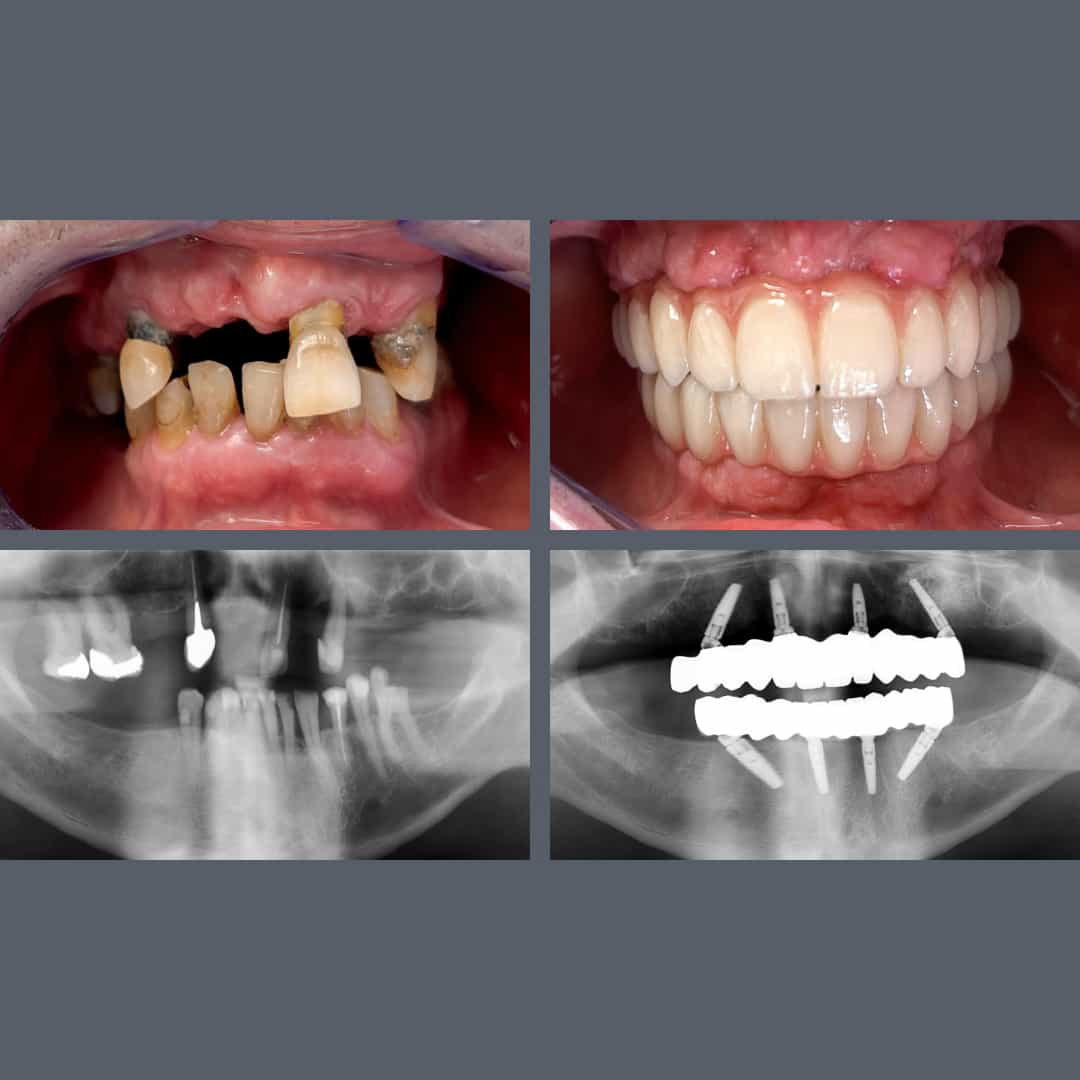

Tandkødssygdom, tandtab, løse tænder – All-on-4® er løsningen!